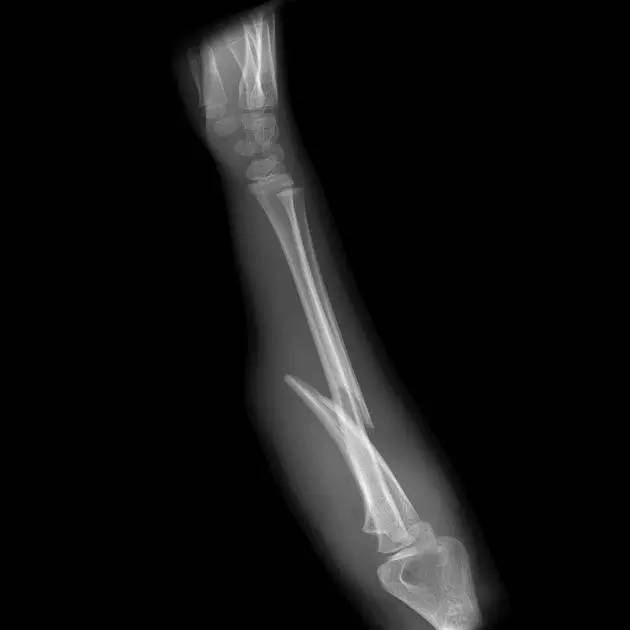

9. Monteggia 骨折(孟氏骨折)

尺骨近端 1/3 骨折合并桡骨头半脱位。

(来源:Radiopaedia)

成人 Monteggia 骨折

儿童 Monteggia 骨折